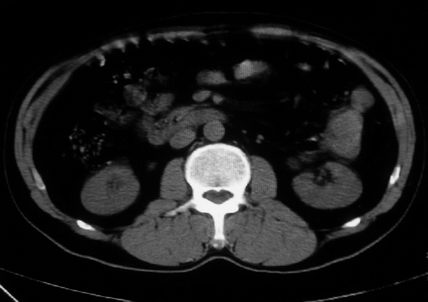

男,体查发现右肝低密度,右肾高密度结节影。高密度ct值92hu,囊肿?

肝右叶囊肿或血管瘤?右肾高密度囊肿。建议增强。

肝右叶圆形低密度灶,考虑囊肿或血管瘤,建议ct增强检查;右肾包膜下高密度圆形灶,考虑:囊肿并出血

肝肾囊肿,不除外两肾积水